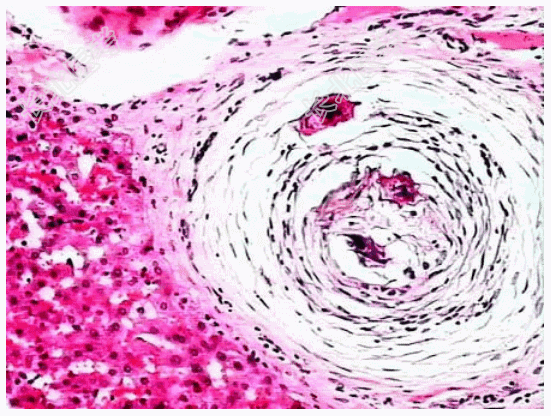

- [材料题] 患者,男,50岁,湖南岳阳人。因贫血、白细胞、血小板减少并腹水入院,临床诊断为“肝硬化”。肝穿刺活检镜下观如图所示,临床拟诊血吸虫性肝硬化。

- 简答题2、该疾病病理学改变表现为?